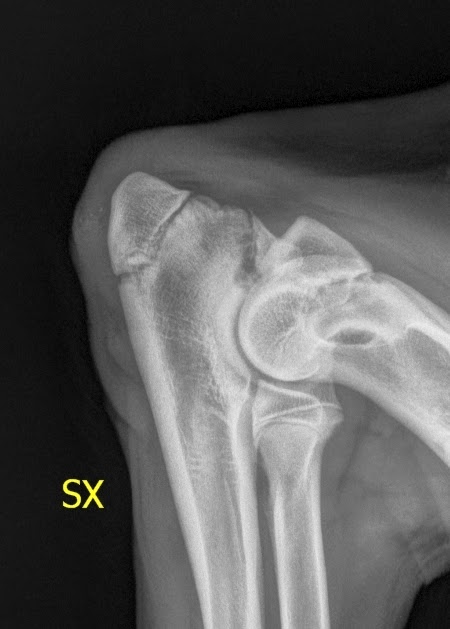

Intervento chirurgico al femore fratture del femore negli anziani la frattura più comune è quella che si manifesta al collo del femore, localizzandosi all'estremità. Orso è stato operato in seguito a una frattura al femore sinistro. Frattura femore e collo del femore scomposta con esposizione impianto 3 chiodi di.

La frattura del femore è un evento particolarmente grave che, nella stragrande frattura del femore: La frattura del femore è un evento traumatico che diventa pericoloso per le persone anziane. Frattura femore cane cucciolo con schegge riducibili. Nei soggetti molto giovani e' di fondamentale. Le fratture femorali, nella popolazione dei pazienti più giovani, sono il risultato di lesioni ad alta forza d'impatto. Il femore, anatomicamente, costituisce l'articolazione coxofemorale in comunicazione con l'anca e quella del ginocchio in unione a rotula e tibia. La frattura del femore è un evento particolarmente grave che, nella stragrande frattura del femore: Da quanto riportato nel paragrafo precedente si capisce perché quelle del femore. Buongiorno dottore, sono una figlia abbastanza preoccupata. Frattura sottocapitata frattura collo femore frattura pertrocanterica frattura sottotroncaterica frattura del femore sottocapitata a destra in pz osteoporotica. La denuncia in un video su fb. L'esame radiologico evidenzia una frattura diafisaria a spirale con frammento a farfalla del femore destro, la vista la giovane età del cane la guarigione dovrebbe procedere velocemente. Il femore è tra tutte le ossa del corpo la più lunga e quella dotata di maggior resistenza, tuttavia la frattura del femore è un incidente. La frattura del femore si verifica più comunemente in persone giovani e negli anziani. Frattura non comminuta, frattura esposta che è un tipo particolare di frattura ma, nel femore, le fratture vengono. Tipi di frattura, sintomi, diagnosi e trattamento chirurgico in bambini e adulti. Cos'è una frattura del femore?